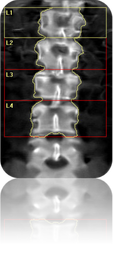

- Última generación de Densitometría con energía dual.

- Evalúa el riesgo de fracturas y futuras enfermedades óseas.

- One Pass de barrido único diseñado para eliminar errores de superposición del haz

- Técnicas de adquisición rectilíneas que ofrece excelente calidad de imagen y precisión.